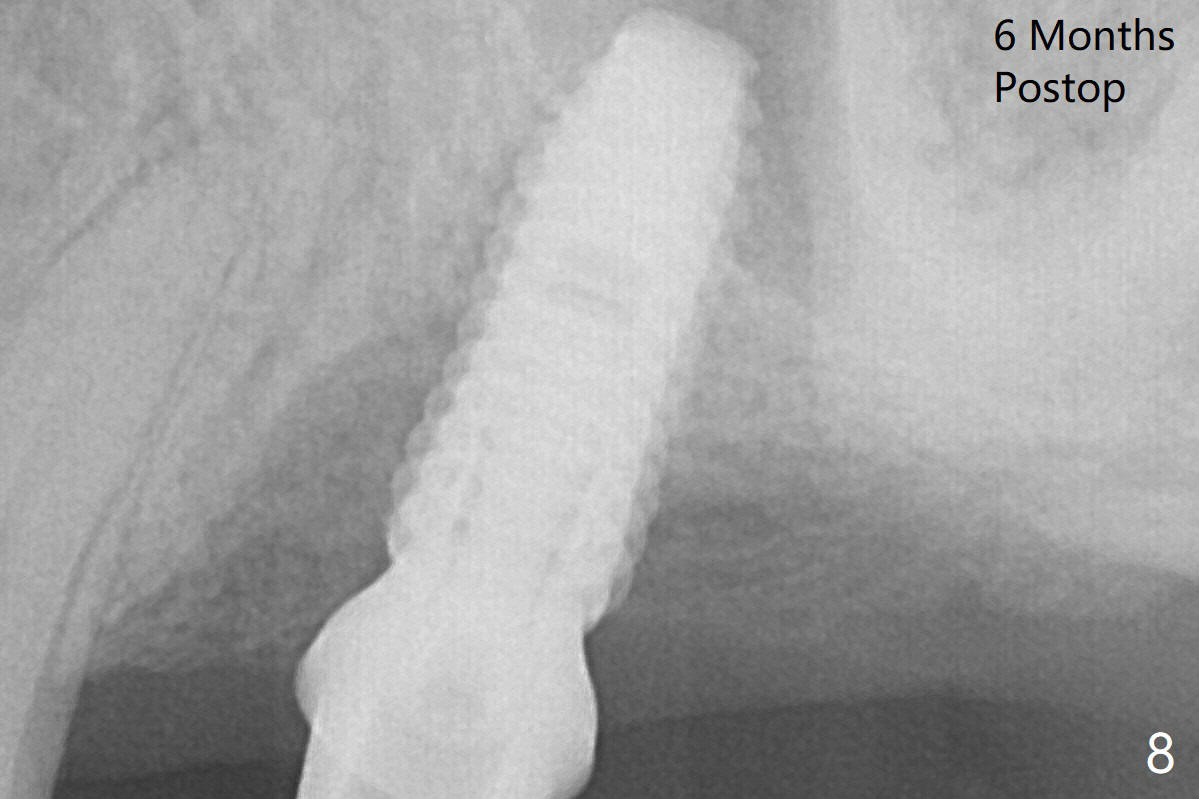

When a 4.5x11.5 mm implant is placed (>35 Ncm), palatal threads are exposed, to which autogenous bone and Vera Graft (Fig.5 *) are placed with a 5.5x5(3) mm abutment. The distal implant threads remains exposed 6 months postop; it appears that the distal socket wall (Fig.7 <) has resorbed (Fig.8). That is a probable reason that the distal threads are exposed. The sockets heal 1 year 7 months post cementation (Fig.9).